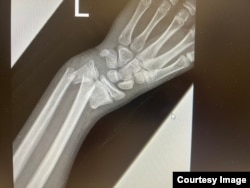

Izgled slomljene ruke nakon TikTok izazova koju je u viber grupi podijelo Vijeće roditelja KS. Radi se, kako je navedeno, o lomu podlaktice kod djeteta.

"Mi smo prije neki dan imali intervenciju u jednoj srednjoj školi, zbog povreda ruku djeteta koje je učestvovalo u tom izazovu. Riječ je o prelomu obje kosti podlaktice sa pomjeranjem kostiju. Nekad se te povrede mogu liječiti samo gipsom, a u nekim slučajevima i operativno. Iz čak dvije osnovne škole dovedeno je dvoje djece koja su povrijeđena u ovom izazovu", kaže za RSE, Riada Blažević, doktorica u Zavodu za hitnu medicinsku pomoć.